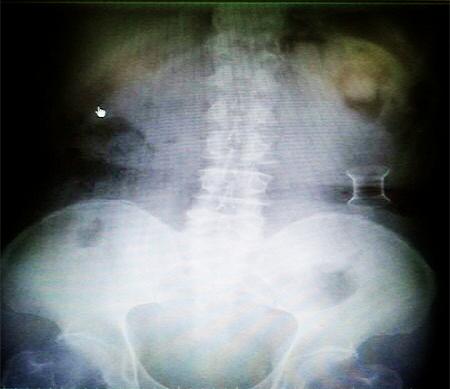

受試患者在結(jié)腸端端吻合術(shù)中,使用我司新研制產(chǎn)品達(dá)到了理想的預(yù)期效果。患者術(shù)后7天、14天X光片顯影,可降解腸道支架均能按研制設(shè)計的預(yù)期時間節(jié)點(diǎn)保持應(yīng)有強(qiáng)度,術(shù)后21天X光片顯示可降解腸道支架已完全破碎,并排出體外。在整個試驗(yàn)過程中,病患無任何不良反映,耐受良好。